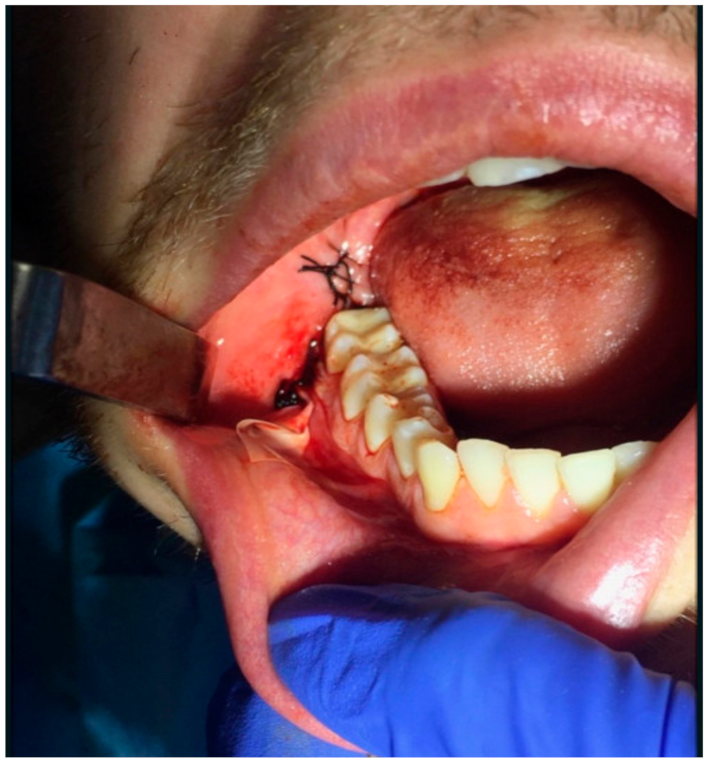

2.2. Surgery